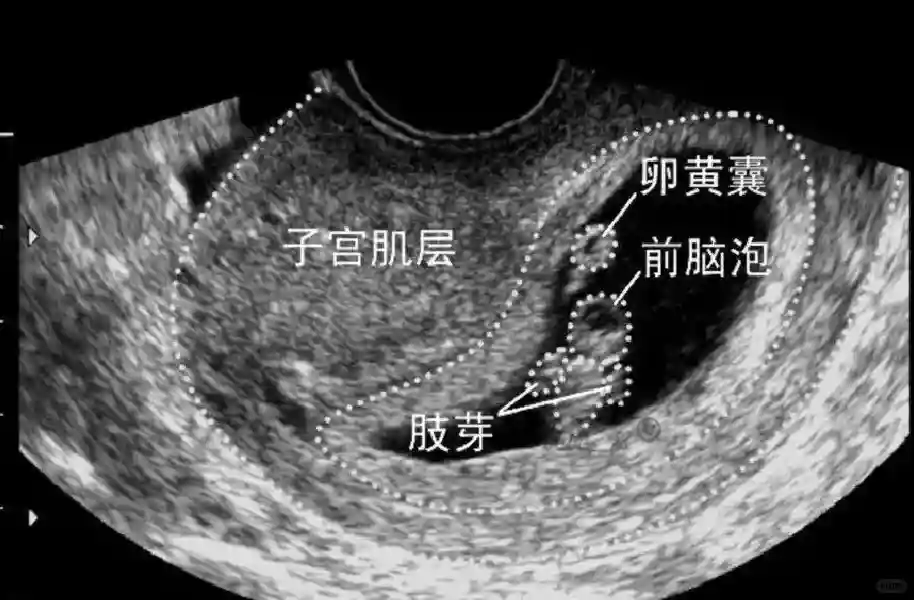

2??卵黄囊:是妊娠囊内第一个解剖结构,直径<7mm。表现为小环状,中央为无回声,囊壁薄,内透声好。卵黄囊位于胚胎旁胚外体腔内。卵黄囊通常在孕5-6周时出现,5-10周稳步增长,一般不超过7mm,至12周消失。妊娠囊的大小与卵黄囊之间有一定关系,妊娠囊平均直径> 8 mm 时,经阴道超声均应显示卵黄囊,妊娠囊平均直径> 18 mm 时,经腹超声均应显示卵黄囊。

3??胚胎:胚胎通常在6-7周时可以为超声显示,起初为胎芽,表现为卵黄囊一侧局部组织增厚,达到1 -2 mm 时才有可能为超声测量出来。达4-5mm时可见胎心搏动,相应孕周为6-6.5周,妊娠囊大小为13-18mm。胚芽长度≥7㎜时仍未见心管搏动,提示胚胎停止发育。胚胎的出现和妊娠囊直径的关系:妊娠囊直径> 16 mm 时,经阴道超声应显示胚胎。妊娠囊直径> 25 mm 时,经腹超声均应显示胚胎。

5??羊膜:早孕期羊膜囊菲薄,超声常不能显示。孕7周以后加大增益或者用高频超声可以显示羊膜。羊膜囊位于绒毛膜内,胚胎位于羊膜囊内。随着胚胎增长,羊水增多,羊膜囊增大,孕12-16周时,羊膜与绒毛膜全部融合,胚外体腔消失。宫腔线一侧内膜内一圆形增强回声区,中央有小囊状液性暗区,宫腔线局部突起变形,称蜕膜内征,用于判断早早孕。